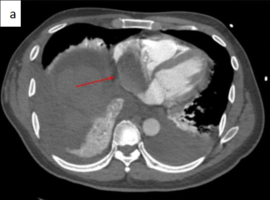

Citation: Van Loo AM, Rempakos A, Fisher SRD, et al. Right Atrial Metastasis from Hepatocellular Carcinoma Leading to Submassive Pulmonary Embolism: An Uncommon Clinical Presentation. Case Rep Clin Cardiol J. 2026; 6(2): 177.